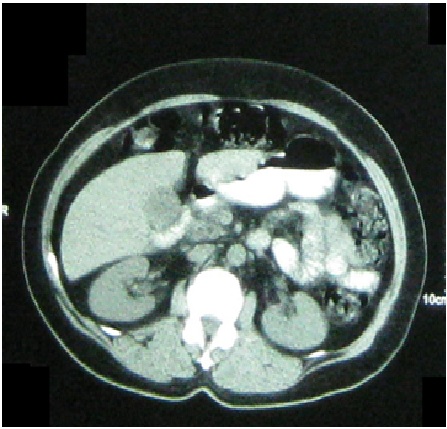

Os tumores estromais gastrointestinais (GISTs) são os tumores mesenquimais mais frequentes do tubo digestivo. São tumores originários das Células Intersticiais de Cajal. Podem acometer qualquer segmento gastrointestinal, predominando no estômago e jejuno, porém no duodeno é uma localização rara, ocorrendo em torno de 3% a 5% dos pacientes acometidos por GIST. Entre 10% a 30% são completamente assintomáticos, sendo descobertos acidentalmente durante endoscopia, diagnósticos radiológicos e até durante intervenções cirúrgicas devido a várias razões. Se presente, os sintomas clínicos são inespecíficos e incluem: cólica abdominal, sensação de saciedade precoce, flatulência, prolongado sangramento gastrointestinal, anemia de origem desconhecida, perda de peso, vômitos e abdômen agudo. Na tomografia computadorizada, que é considerada como técnica de referência, os GISTs se apresentam tipicamente como massas grandes, bem delimitadas, heterogêneas e, às vezes, exofíticas. Para o seu tratamento, preconiza-se a exérese cirúrgica.